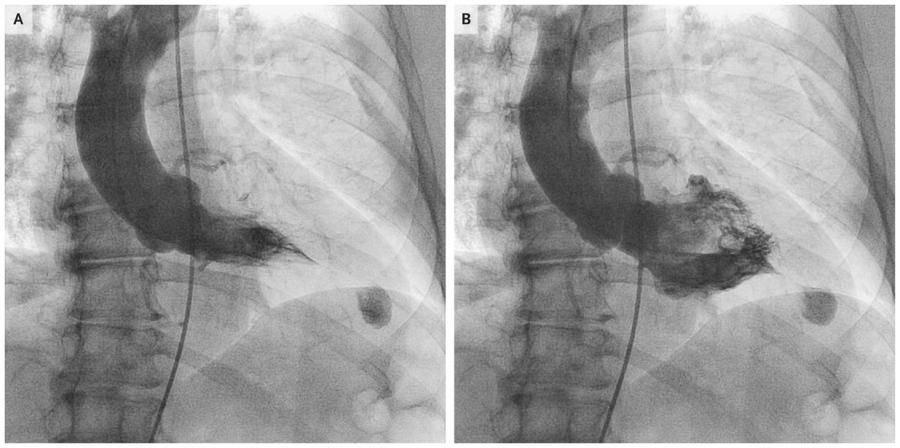

3. 左室造影:

对心尖肥厚型心肌病患者行右前斜30°左心室造影可见舒张期左心室呈特征性“黑桃样”形改变,心尖部心肌明显肥厚;

-

收缩期可见心尖腔部位完全闭塞。

似扑克牌“黑桃”形改变,尖部向右下

影像学检查见舒张期左心室呈特征性“黑桃样“,收缩期显著的心尖腔消失;